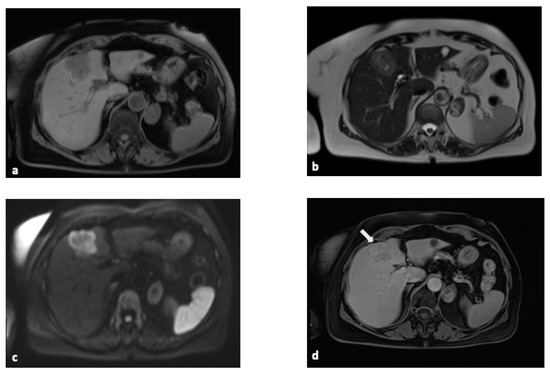

2.3. Magnetic Resonance Imaging (MRI)

- Jhaveri, K.S.; Hosseini-Nik, H. MRI of cholangiocarcinoma. J. Magn. Reson. Imaging 2015, 42, 1165–1179. [Google Scholar] [CrossRef] [PubMed]

- Kang, Y.; Lee, J.M.; Kim, S.H.; Han, J.K.; Choi, B.I. Intrahepatic mass-forming cholangiocarcinoma: Enhancement patterns on gadoxetic acid-enhanced MR images. Radiology 2012, 264, 751–760. [Google Scholar] [CrossRef] [PubMed]

- Engelbrecht, M.R.; Katz, S.S.; van Gulik, T.M.; Laméris, J.S.; van Delden, O.M. Imaging of perihilar cholangiocarcinoma. AJR Am. J. Roentgenol. 2015, 204, 782–791. [Google Scholar] [CrossRef]